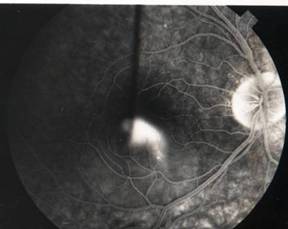

TOXOPLASMOSIS |

Toxoplasmosis is a disease provoked by the obligate intracellular protozoan Toxoplasma gondii. It is found in a variety of mammal and bird hosts. The most common intermediate host is the cat. It is one of the most frequent causes of retinochoroiditis in humans, with more than 60 percent of the United States population and up to 75 percent of the world's general population possessing some seropositive findings Etiology

Ophthalmic Features